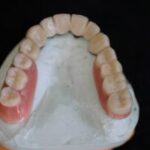

Auf Druckknöpfen gestützte Oberkiefer-Totalprothese, dadurch fester Sitz, kleinere Gaumenauflage